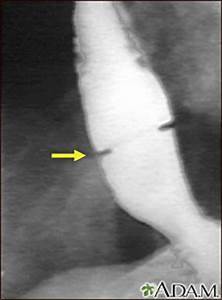

Paciente com disfagia intermitente para grandes pedaços

Anel de Schatzki

(estreitamento laminar do corpo do esôfago)

Síndrome de Steakhouse

Como é o diagnóstico de Anel de Schatzki e o tratamento

Esofagografia baritada

Dilatação endoscópica